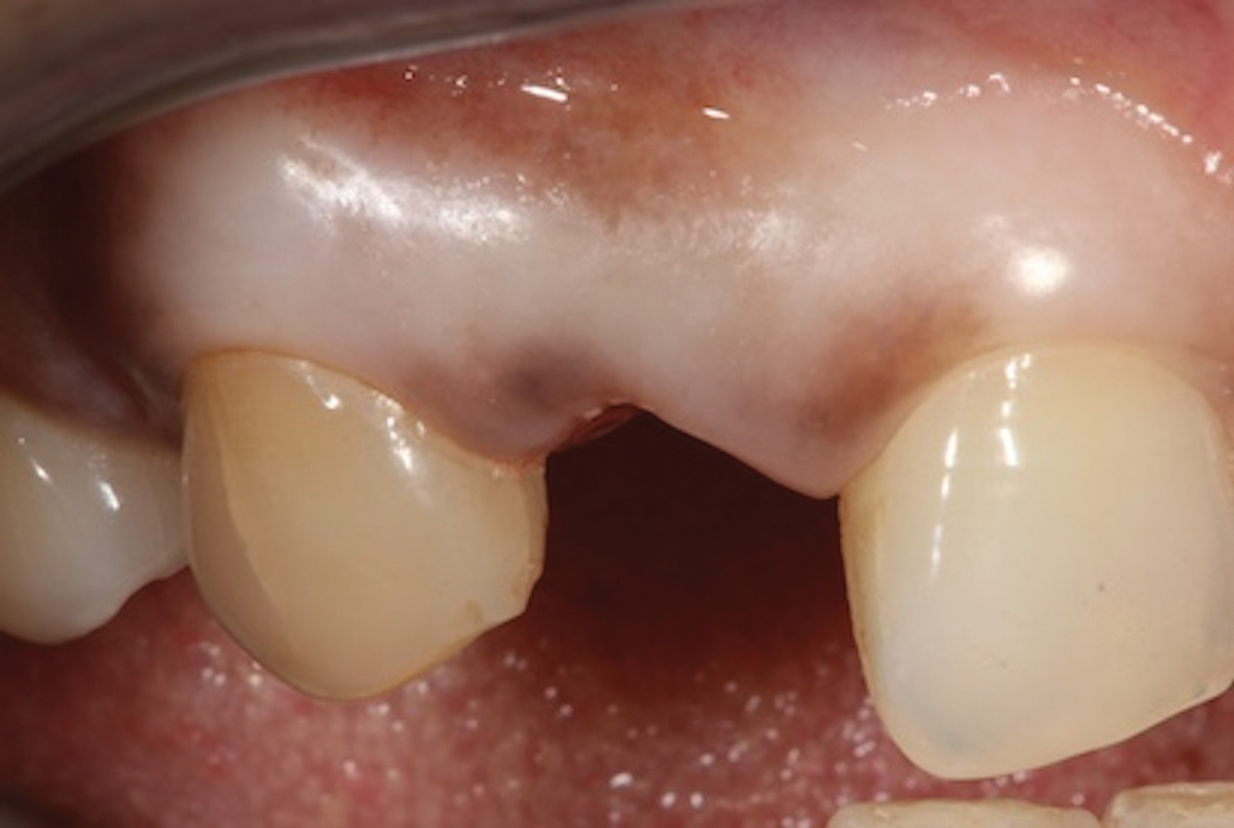

In the example case presented, the patient returned for evaluation 3 months after implant placement and delivery of the fiber-reinforced composite bridge, and the soft tissue at the site demonstrated adequate growth over the resin pontic (Figure 14). This would provide for a favorable esthetic outcome when the final implant-supported crown was ultimately delivered.

(14.) Three-month posttreatment close-up right lateral view of the final bridge. Note how the soft tissue at the site demonstrates adequate growth over the resin pontic, which will later translate into excellent esthetics for the implant-supported crown.

Figure 14